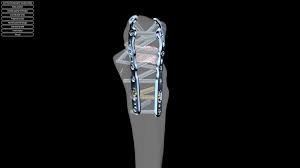

Il existe plusieurs façon de fixer l’olécrane :

Brochage haubanage

Plaque unique

Plaques multiples